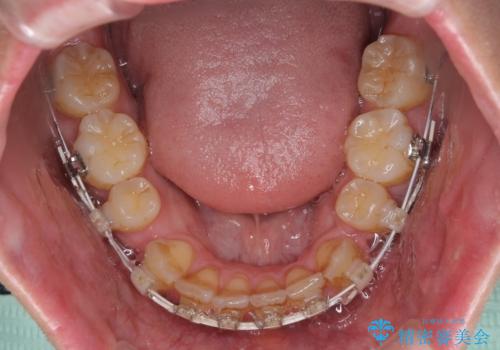

- 矯正装置

- ハーフリンガル

目立たない装置を希望されたので、上顎が裏側装置のハーフリンガルを選択し、上下左右の小臼歯(計4歯)を抜歯して矯正治療を行うこととしました。

上下顎で左右差の大きい抜歯矯正を裏側装置で行ったため、非常に時間がかかりましたが、正中位置も良い位置に改善され、気になっていた突出感も解消されました。